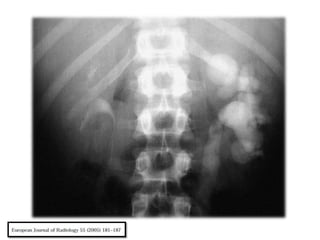

En la radiografía simple, un tamaño renal variable puede

apreciarse.

Las Calcificaciones, que ocurren en más de 50% de los

pacientes, puede adoptar varias formas. Pueden ser

focales, que se producen en los restos de caseum, o como

cálculos en el sistema colector.

En los casos de tuberculosis en fase terminal, las

calcificaciones características que muestra una distribución

lobar son menudo encontradas.

En última instancia, un riñón totalmente calcificado y no util

puede verse, que representa etapa final de

enfermedad, denominada autonefrectomia.

Hallazgos coexistentes, tales como lesiones

destructivas de los cuerpos vertebrales y

calcificaciones de los tejidos y los músculos

paravertebrales (psoas) el contexto de un

absceso frío, se pueden encontrar.